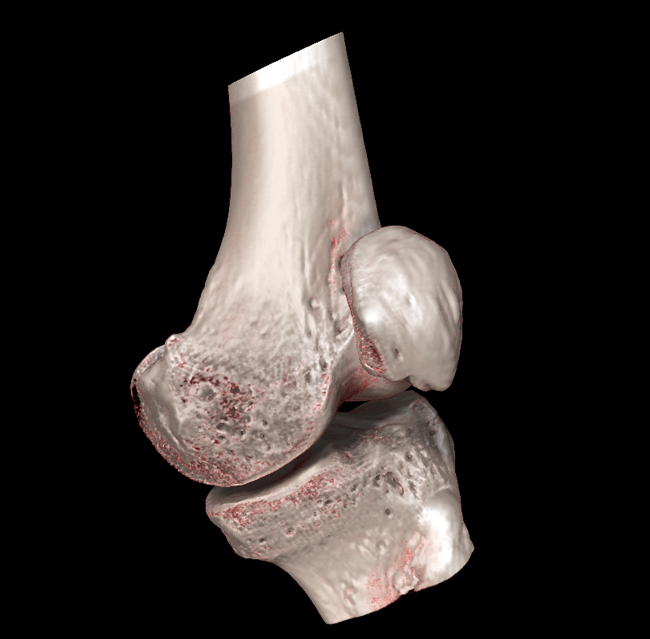

HRCT

High Resolution Computed Tomography. Outstanding image quality with a voxel size up to 100 µm